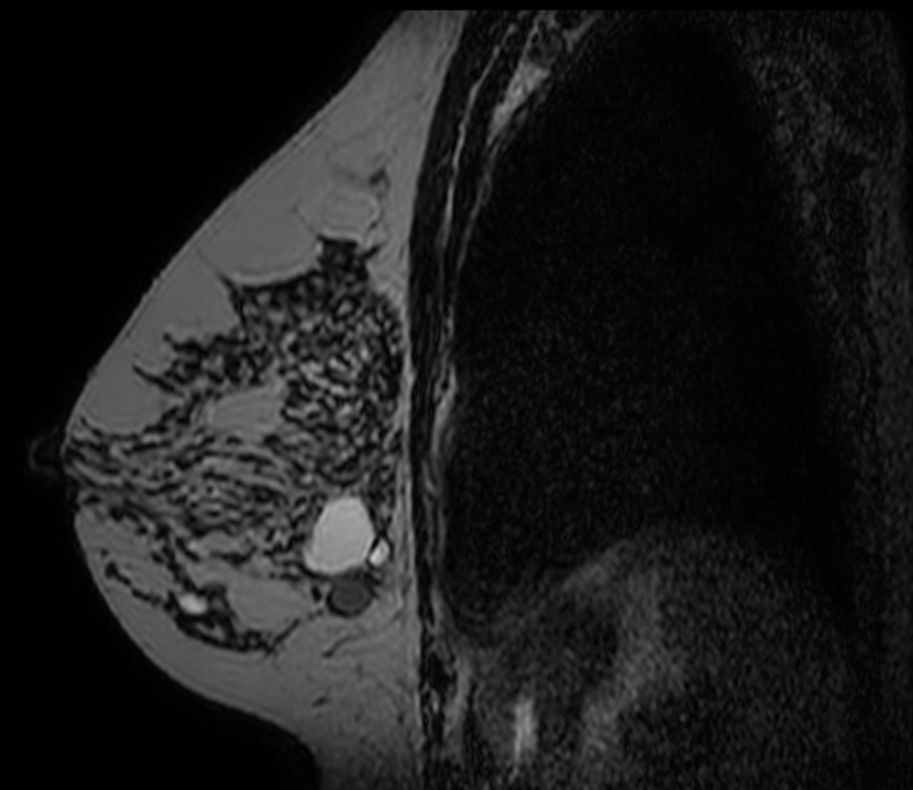

Axial 3D T2w BreastVIEW

3D T2w BreastVIEW (coronal reformat)

3D T2w BreastVIEW (sagital reformat)

3D Breast imaging lets you acquire high resolution data in multiple directions, including oblique, in one scan helping you enhance your confidence when diagnosing lesions. 4D FreeBreathing provides dynamic information with a high temporal resolution, allowing contrast-enhanced MRI breast studies.